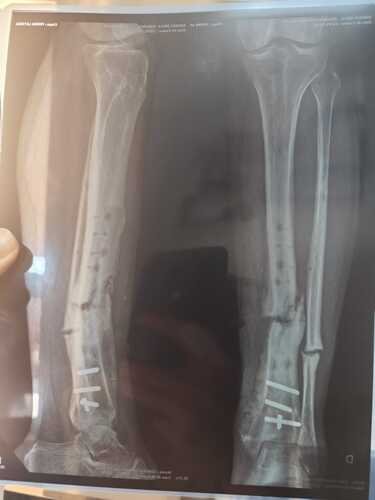

Eu sofri um acidente dia 30 de janeiro de 2024, onde passei por 3 cirurgias no SUS onde duas foram colocados haste e por dentro do osso e a terceira foi colocado placa essa foi realizada no dia 28/03/2025 e nessa deu a famosa rejeição de onde venho tomando antibiótico a mais ou menos 6 meses me gerando um custo de cada 7 dias de 90 reais o nome dele é LEVOFLOXACINO 750MG, E continuo com essa inflamação no local da cirurgia e nenhuma das três fez a consolidação óssea. E foi feito uma última cirurgia agora em dezembro de 2025 para remover a placa por conta da inflamação, mas mesmo removendo a placa a inflamação continua, agora o motivo segundo o meu médico é que minha perna está quebrada o osso esta totalmente mole.

Então preciso fazer essa reconstrução óssea que é famosa GAIOLA, fixador externo ou Ilizarov, então venho pedir ajuda sua com muito amor e carinho para me ajudar na arrecadação para realizar essa cirurgia, pois o SUS não me dá uma solução e nem previsão dessa cirurgia, pois o médico que realiza tal cirurgia em Umuarama, só pode realizar a cirurgia partir de julho e olha lá e não posso esperar até lá por conta dessa inflamação local que pode dar infecção no meu sangue e até poder perder a perna, então pessoa sua ajuda.Sou Casado, tenho 2 filhos um de 6 anos e um de 3 anos e ambos me perguntam todo dia pai, quando sua perna vai sarar para nós brincarmos, é tão dolorido você ouvir isso dos seus filhos e vendo eles brincarem com outras pessoas por que você não consegue correr, andar de bicicleta com eles, ao dormir eles falam pai reza pela sua perna para sarar logo. Que isso seja um motivo a mais para me ajudar com esse tratamento. Já falei com vereadores, com pessoas do ministério publico e ninguém consegue me dar um prazo e nem solução para resolver tal problema.Caso a cirurgia saia pelo SUS o valor será destinado ao meu tratamento com medicamento pós-cirúrgico e também fisioterapia. E se sobrar será destinado a UOPECCAN de Umuarama.